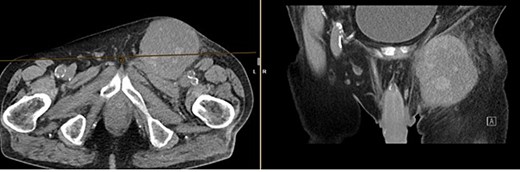

The CT of the abdomen showed a highly suspicious malignant mass in the left groin area (Fig 3). Additionally, nearby satellite lesions were detected, interpreted as lymph nodes. During a more thorough physical examination, a hazelnut-sized, highly suspicious malignant lesion was identified on the glans penis. Upon detailed anamnesis, the patient reported a previous circumcision surgery with carcinoma detection.

Finding from CT of the abdomen: highly suspicious malignant mass in the left groin area, with nearby satellite lesions, DD lymph nodes.